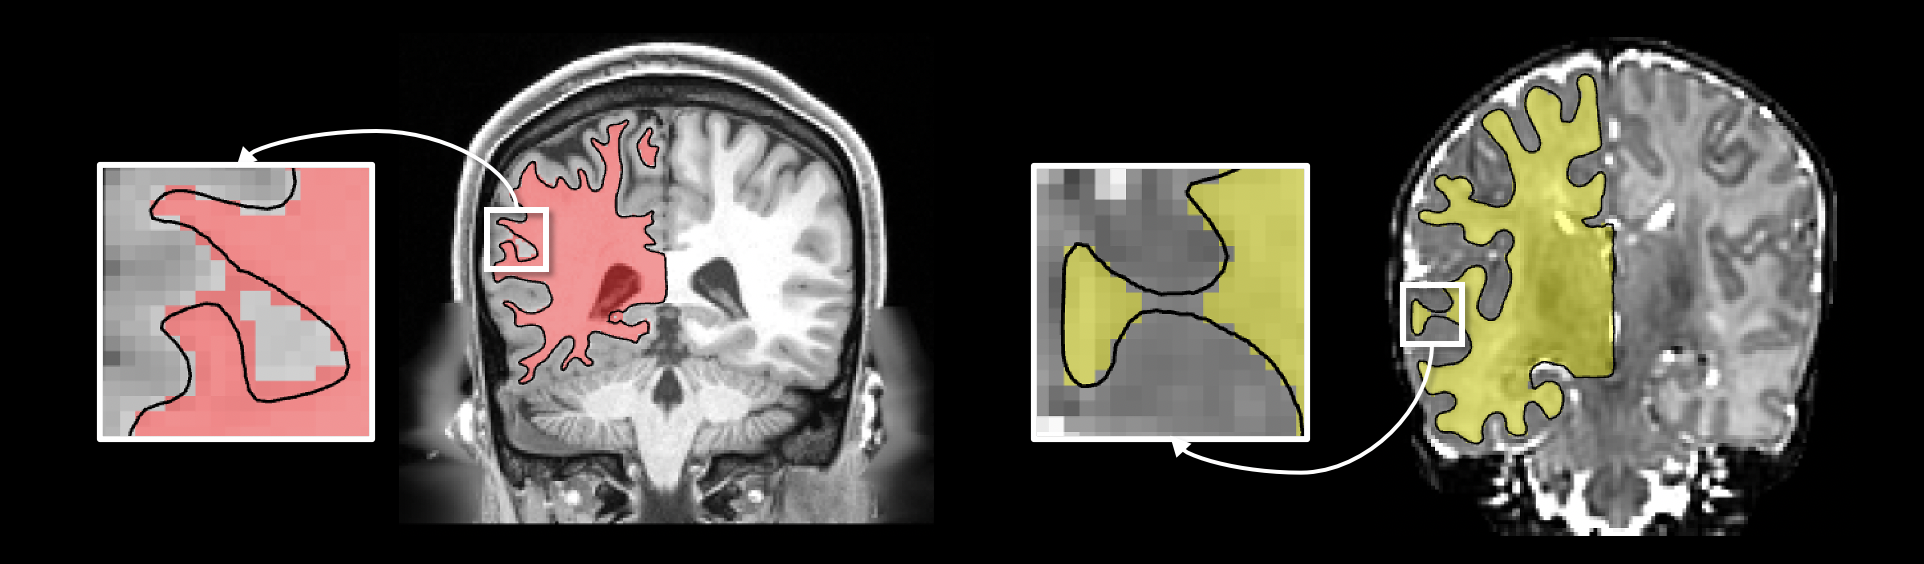

Refer to caption

Figure 4: Left: A discrete SDF. The red bounding box marks the initial points for the original topology correction algorithm [25]. The black contour marks the initial points on the boundary 𝒮λ^superscript𝒮^𝜆\mathcal{S}^{\hat{\lambda}} for our improved version. Right: The topology correction result with boundary 𝒮λ^=16superscript𝒮^𝜆16\mathcal{S}^{\hat{\lambda}=-16}.

3.3 Topology Correction

To guarantee spherical topology of the implicit surfaces, we apply the topology correction algorithm by Bazin et al. [25] to the discrete SDF 𝒰dsubscript𝒰𝑑\mathcal{U}_{d}. The algorithm [25] adopts a topology-preserving fast marching approach to fix the topology of the surfaces 𝒮λsuperscript𝒮𝜆\mathcal{S}^{\lambda} defined by 𝒰𝒰\mathcal{U} under any level λ𝜆\lambda. However, since the original implementation [25, 18] is computationally intensive, we re-implement and improve the original algorithm, which is consequently accelerated by a factor of 202020.

In addition, we improve the initialization of the original algorithm [25]. To fill the holes or handles in the input level set, the original algorithm [25] starts topology correction from initial points on the boundary of the level set, which is shown as the red bounding box in Figure 4. The algorithm processes the voxels iteratively from lower level to higher level. Therefore, only the voxels inside the boundary need to be processed. For cortical surface extraction, since we consider one brain hemisphere at a time, instead of correcting the topology of the entire level set, we only need to process the voxels inside a λ^^𝜆\hat{\lambda}-level surface 𝒮λ^superscript𝒮^𝜆\mathcal{S}^{\hat{\lambda}} for λ^<0^𝜆0\hat{\lambda}<0. This not only accelerates the runtime but also ensures that the 0-level surface, i.e., the WM surface, has desired topology.

To obtain the boundary points of the surface 𝒮λ^superscript𝒮^𝜆\mathcal{S}^{\hat{\lambda}}, we first create a binary mask containing all voxels inside the surface 𝒮λ^superscript𝒮^𝜆\mathcal{S}^{\hat{\lambda}}. More precisely, the voxel of the binary mask is set to one if its level λ𝜆\lambda satisfies λλ^𝜆^𝜆\lambda\geq\hat{\lambda}. Then, we apply morphological dilation to enlarge and expand the binary mask. The dilated voxels represent the boundary of 𝒮λ^superscript𝒮^𝜆\mathcal{S}^{\hat{\lambda}}, which is illustrated as the black contour in Figure 4. These boundary voxels are used as initial points by topology correction algorithm, and the values of the voxels outside the boundary are set to λ^^𝜆\hat{\lambda}. Figure 4-Right shows a topologically corrected result with λ^=16^𝜆16\hat{\lambda}=-16. The initialization avoids processing of 76%percent7676\% of the voxels. Such an accelerated topology correction algorithm only needs one second to process a volume of size 192×224×192192224192192\times 224\times 192.